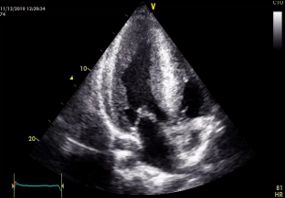

Ecocardiograma transtoracico con el mejor equipo de la región

• Ecocardiografía